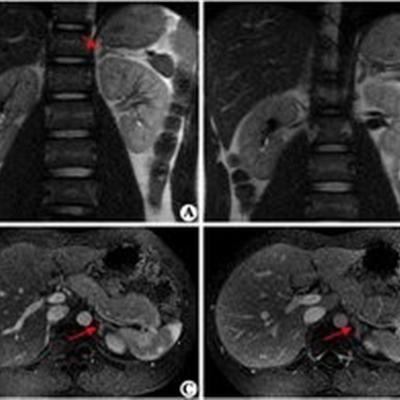

首先,肾上腺增生,主要由于肾上腺皮质激素生物合成过程中所必需的酶存在缺陷,致使皮质激素合成不正常。

然后,其临床表现为多数病例肾上腺分泌理糖激素、理盐激素不足而雄性激素过多。

最后,临床上出现不同程度的肾上腺皮质功能减退,伴有女孩男性化,而男孩则表现性早熟,此外尚可有低血钠或高血压等多种症候群。